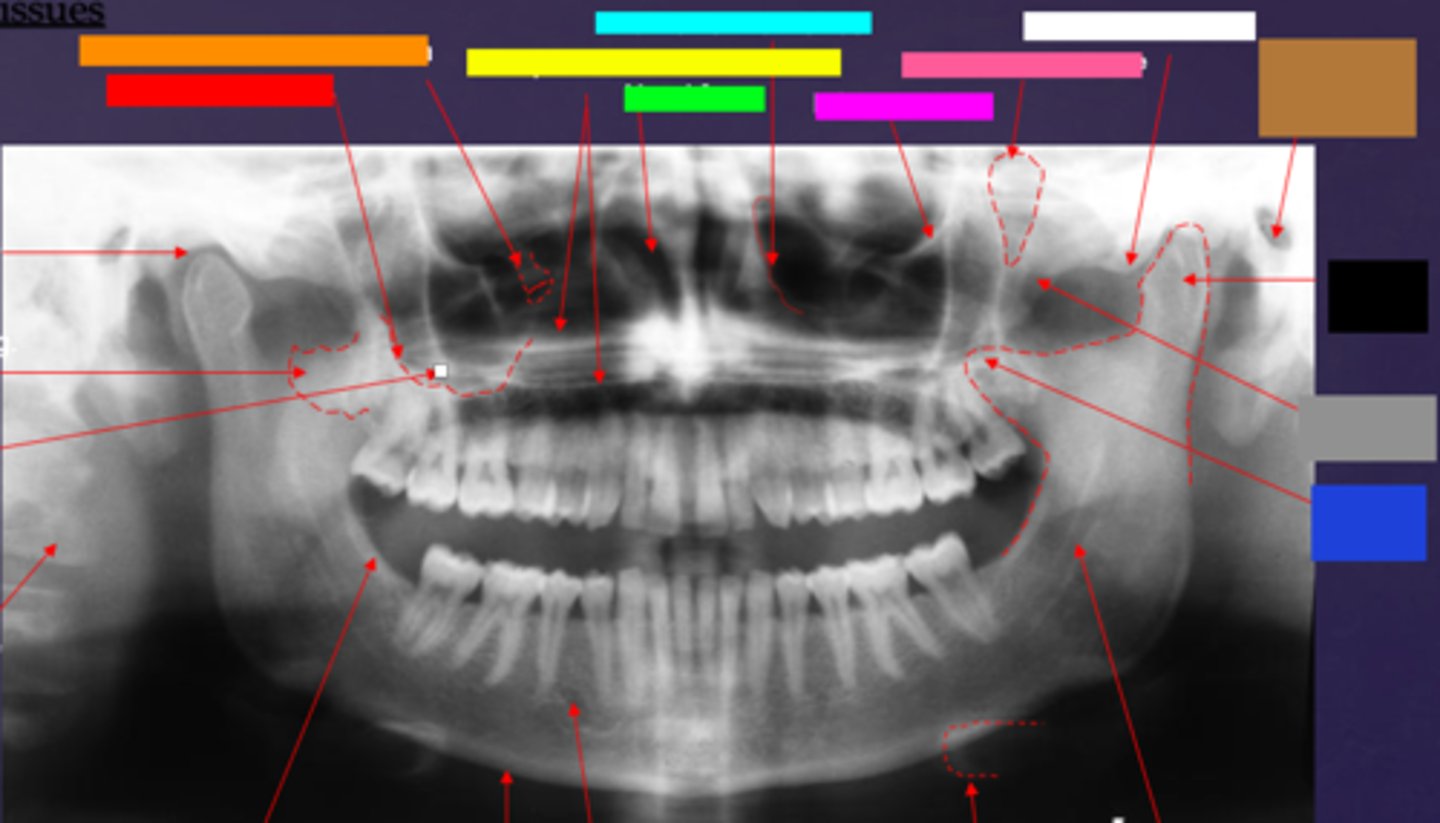

ID the hard tissue anatomy indicated by the arrow pointing from the red box:

floor of max. sinus

ID the hard tissue anatomy indicated by the arrow pointing from the orange box:

infra orbital canal and foramen

ID the hard tissue anatomy indicated by the arrow pointing from the yellow box:

hard palate/floor of nasal fossa

ID the hard tissue anatomy indicated by the arrow pointing from the green box:

nasal fossa

ID the hard tissue anatomy indicated by the arrow pointing from the light blue box:

ant. wall of max. sinus

ID the hard tissue anatomy indicated by the arrow pointing from the dark blue box:

coronoid process

ID the hard tissue anatomy indicated by the arrow pointing from the hot pink box:

infra orbital rim

ID the hard tissue anatomy indicated by the arrow pointing from the pink/salmon box:

pterygomaxillary fissure

ID the hard tissue anatomy indicated by the arrow pointing from the brown box:

external auditory meatus/ear canal

ID the hard tissue anatomy indicated by the arrow pointing from the white box:

articular eminence

ID the hard tissue anatomy indicated by the arrow pointing from the black box:

mandibular condyle

ID the hard tissue anatomy indicated by the arrow pointing from the gray box:

zygomatic bone

mandibular fossa

lateral pterygoid plate

zygomatic process of maxilla

cervical spine

external oblique ridge

inferior boarder of the mandible

mental foramen

inferior alveolar canal

hyoid bone